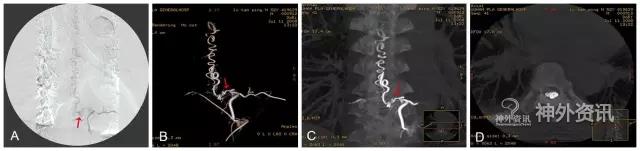

脊髓血管造影,尤其是经皮穿刺股动脉选择性脊髓血管造影,是诊断脊髓血管疾病的金标准。至今,由于影像技术、DSA血管造影机诸多后处理功能的进步,如三维成像技术(three-dimensional imaging technology;图1)、最大密度投影成像(maximum intensity projection,MIP;图2)、双容积重建(double volume,DV;图3)与三维影像融合技术(three dimensional image fusion technology;图4)及我们研究开发的三种技术的动态成像技术(dynamic image fusion technology),可以给出冠状位从前到后再从后到前、矢状位从左到右再从右到左、轴位从上到下再从下到上的全方位多角度动态立体解剖影像(图5),就更提高了对脊髓血管疾病诊断的认识和治疗水平。因此,应该说这些三维融合影像才是脊髓血管疾病诊断的金标准[1,2]。

图1: 左侧T9硬脊膜动静脉瘘(SDAVF),↑示瘘口。A. 2D-DSA;B. 3D-DSA;C、D. 最大密度投影(MIP)冠状位与轴位融合影像。